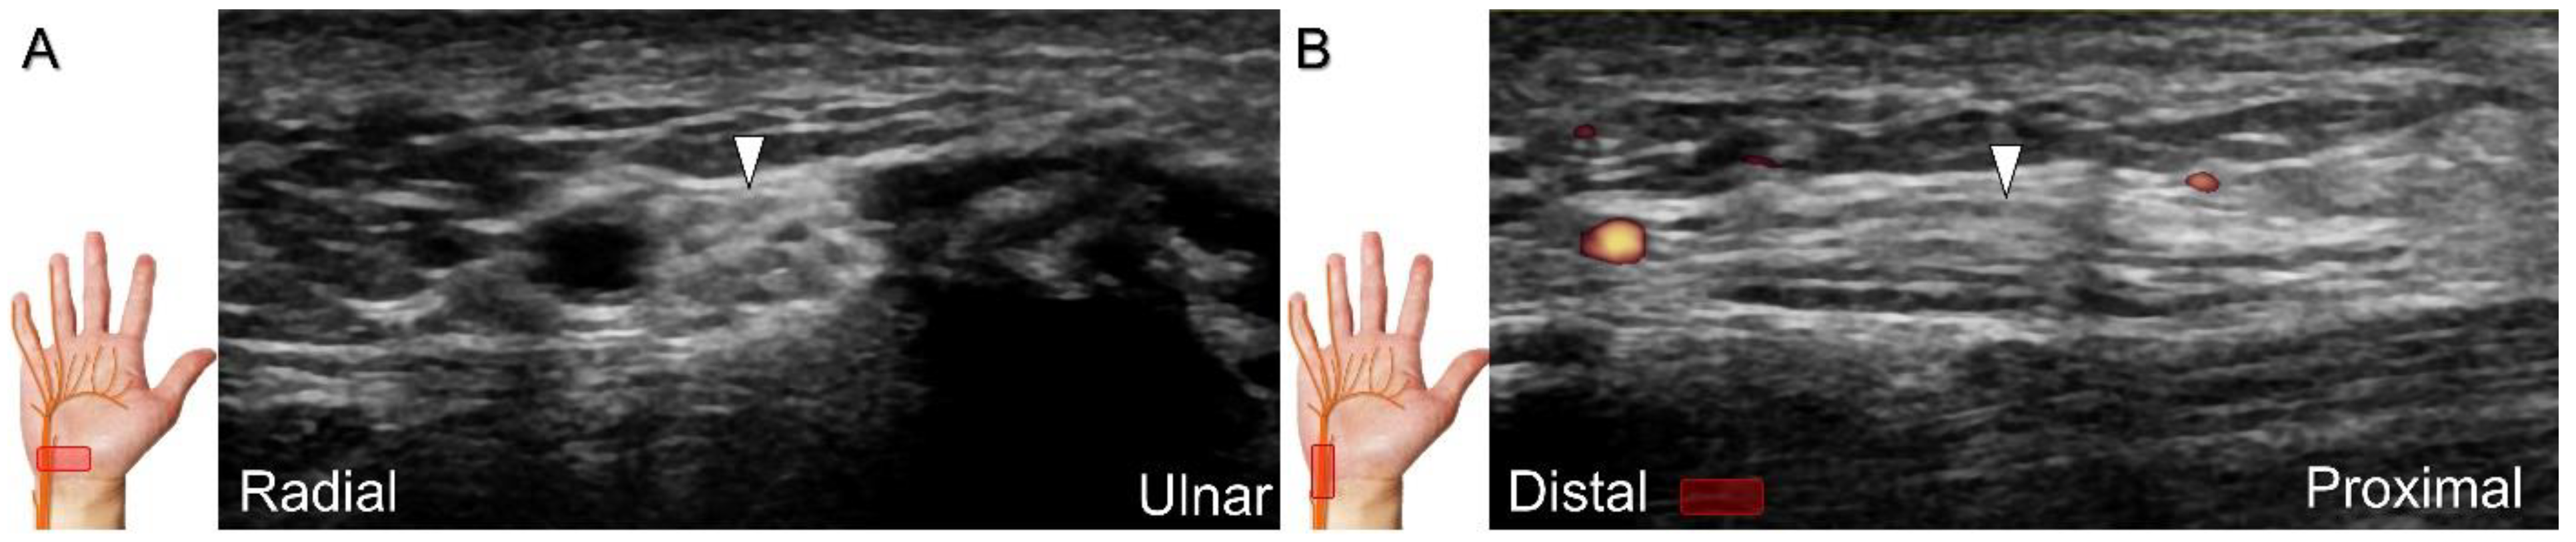

US imaging may reveal a neuroma in cases where patients report chronic allodynia and/or tingling sensation in the affected digit (Figure 36). To perform hydrodissection, the in-plane approach can be utilized in the nerve’s short axis after identifying the extensor digitorum tendons and the dorsal metacarpal arteries (Figure 37).

Figure 37. Ultrasound-guided injection to the dorsal proper digital nerve in its short axis with the dual imaging mode (Doppler vs. B mode). White arrowhead: dorsal proper digital nerve; black arrowhead: dorsal proper digital artery; arrow: needle. T: flexor tendons.